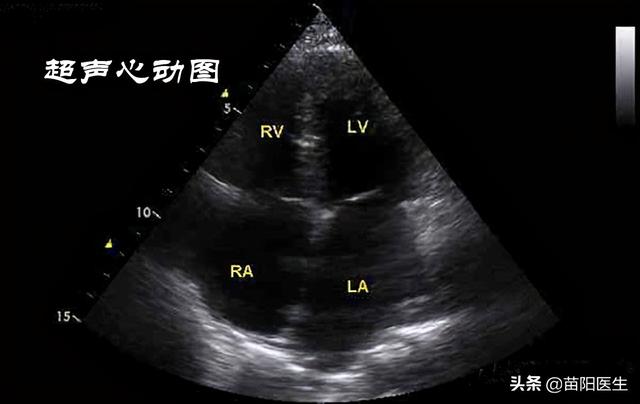

2、超声心动图。主要是用来检查心脏的结构以及运动功能,通过超声心动图检查,不仅可以看到心腔大小、心壁厚度、瓣膜开合等情况,还可以看心肌的运动和血流,能较准确的测定心功能。当人出现胸闷、长期高热、嘴唇发紫等症状时,就需要做超声心动图检查。